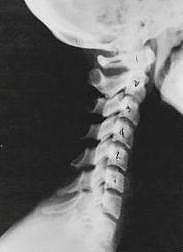

Near Normal

Subluxation Degeneration - Normal This is a side x-ray view of the neck. As with all the pictures you will see on this page, the patient is looking to the right of the screen, so you are viewing the right side of their neck. We will call this picture a "near normal" spine. Compare this spine with the ones you will see below on this page. Notice the normal forward curve of the neck. This curve helps absorb shock. Notice how each of the disc spaces between C2 (second bone in neck) and C7 are thick and even, this again is normal. Also notice how the front portions (right on the x-ray) of each of the vertebrae (called the 'body' of the vertebrae) are fairly square with clear and well defined borders. This type of arrangement is normal in the neck. Normal vertebrae in other parts of the spine also have similar characteristics to what we see here. When subluxations occur and are left uncorrected, ongoing relentless changes occur that result in damage to the structure and function of the spine along with nerve damage and the resulting problems caused from improper nerve supply.